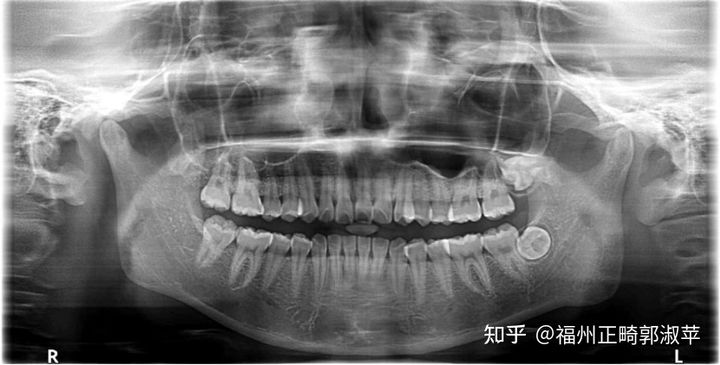

l 全景片示全部牙轴基本平行

此病例为轻度拥挤型病例,同时开唇露齿,咬合不佳及上下中线偏斜等问题,加上全景片显示有18,28阻生,38,48牙胚存在,所以在上下前牙凸面型的情况下选择了 拔牙矫正的方案。

此病例在初诊时前侧貌已经是凸面型双侧磨牙远中关系,所以在选择了拔除上颌第一前磨牙及下颌第二前磨牙的治疗 方案下,内收拔牙间隙的过程中如何轻力的控制前牙内收和调整双侧磨牙咬合,维持后牙牙轴的直立还有改善开唇露齿是本病例的治疗难点